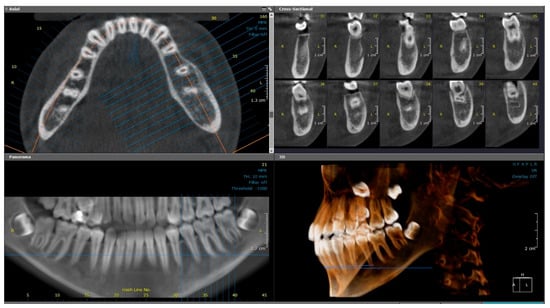

2.1.2. Radiographic Examination

2.2.2. Radiographic Examination

| 1 | 11 | Left mandible (#32–#37) | Mixed sclerotic and lytic lesion with buccolingual expansion and “onion-skin” periosteal reaction | Irregular bone and fibrous tissue, sclerosis, no inflammation or bacteria | Long-term antibiotic course, NSAIDs | CNO confirmed by imaging, histology, and initial failure to respond to antibiotics | Conservative; antibiotics discontinued after improvement | Improved at 7 months; recurrence at 18 months; no further treatment needed |

| 2 | 9 | Right mandible (#33–#47, crossing midline) | Patchy sclerotic and radiolucent lesion, mandibular expansion, double cortex | Viable bone with osteoblastic rimming, no bacterial colonies | Multiple antibiotics, extractions, NSAIDs | CNO based on imaging, histology, and clinical course | NSAIDs only; progressive improvement | Gradual resolution with NSAIDs |